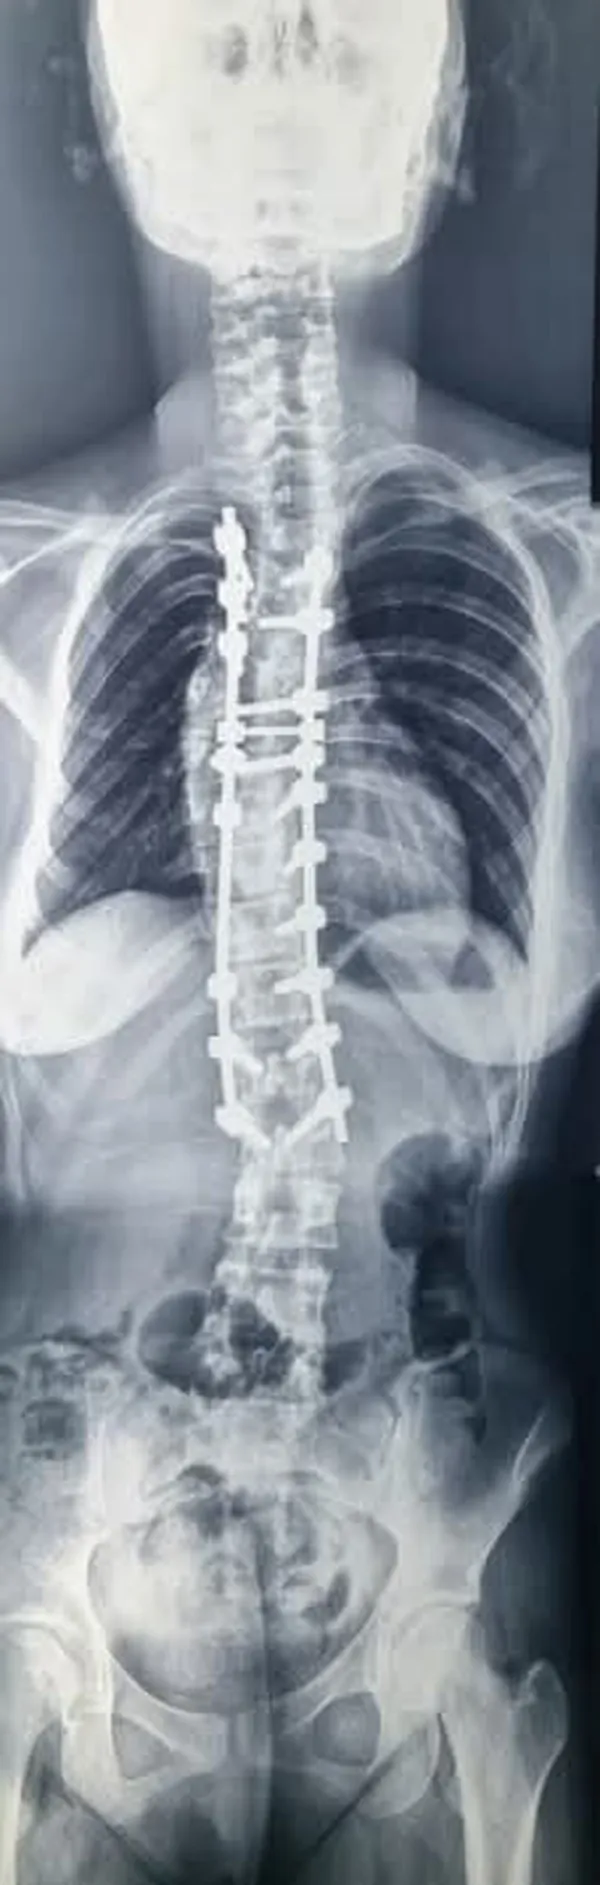

فريق طبي بجامعة بني سويف ينجح في إصلاح اعوجاج بالعمود الفقري لأحد المرضى

أعلن الدكتور طارق على ، القائم بأعمال رئيس جامعة بني سويف، نجاح فريق طبي بقسم جراحة المخ والأعصاب بكلية الطب في إصلاح اعوجاج في العمود الفقري لأحد المرضى، وهو ما يُعد علامة بارزة في مسيرة القسم نحو تقديم خدمة طبية متقدمة، وذلك تحت إشراف الدكتور هاني حامد عميد كلية الطب، والدكتور عماد البنا المدير التنفيذي للمستشفيات.

وأوضح رئيس جامعة بنى سويف، أن الفريق الطبي الذى أجرى العملية الجراحية إصلاح اعوجاج في العمود الفقري لأحد المرضي، ضم الدكتور محمد شعبان محمود، أستاذ ورئيس القسم، والدكتور عبدالرحمن صابر المسؤول عن متابعة جراحات اعوجاج العمود الفقري، وبمشاركة كل من الدكتور مصطفى فكري و الدكتور محمود رمضان.

و هنأ رئيس الجامعة الفريق الطبي على هذا الإنجاز الطبي المتميز، الذي يُعد نموذجًا مشرفًا لما يمكن أن تقدمه الكفاءات الجامعية من خدمات صحية متقدمة، لافتاً إلى أن إجراء هذا النوع من العمليات التدقيقية يعكس مستوى التطور الذي وصلت إليه المستشفى الجامعي من حيث الإمكانيات البشرية والتقنية، مؤكدا حرص الجامعة الدائم على دعم كل الجهود التي تساعد في رفع جودة الخدمات المقدمة للمواطنين.